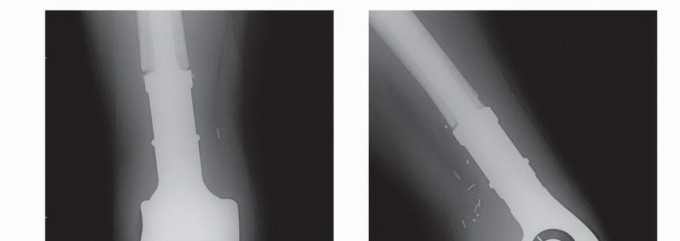

- التثبيت الداخلي (Intramedullary Nailing):

- الوصف: يتم إدخال مسمار معدني طويل مجوف داخل التجويف النخاعي لعظم الفخذ لتقويته وتثبيته.

- الاستخدام: شائع جدًا لتثبيت كسور الفخذ المرضية أو لمنع الكسور في العظام الضعيفة.

- ميزاته: يوفر استقرارًا فوريًا، ويسمح بالتحميل المبكر على الساق.